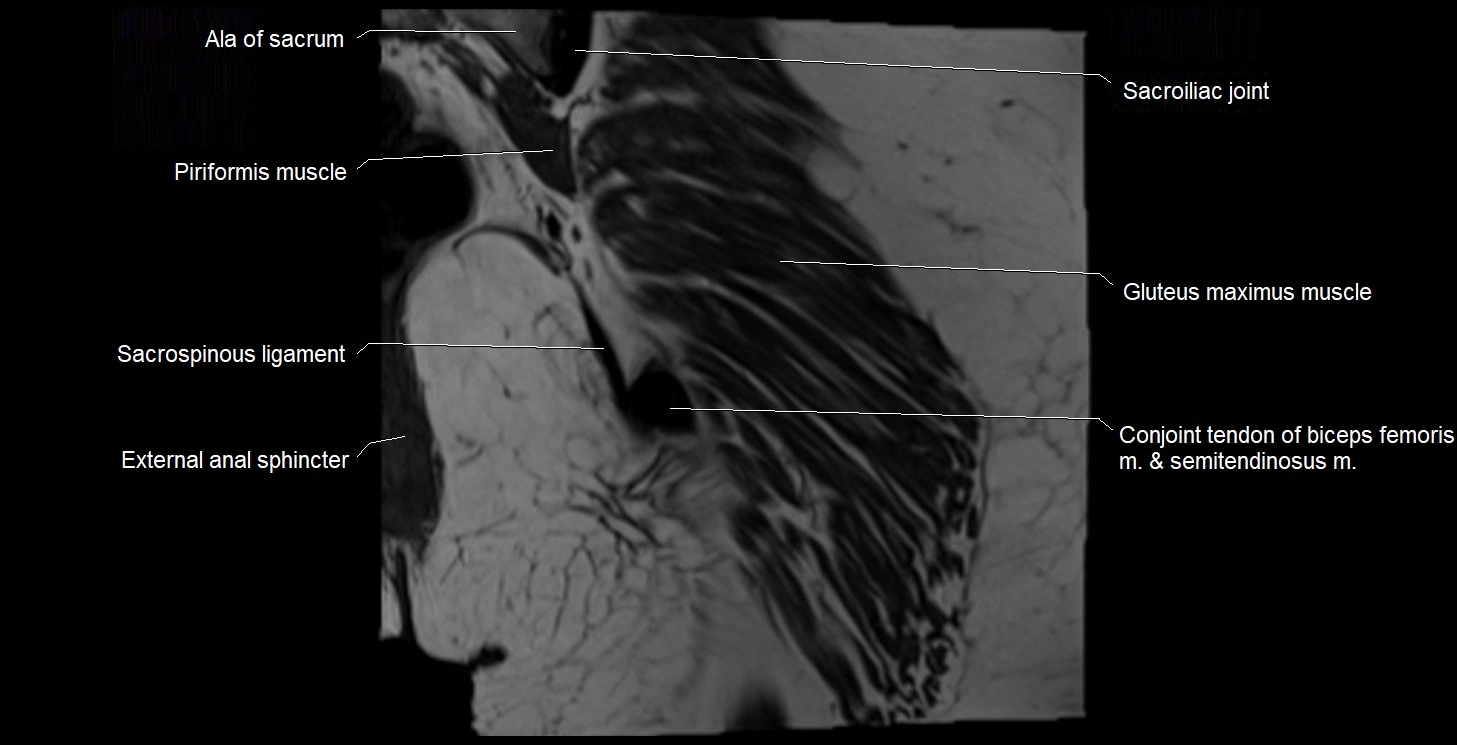

- Ala of sacrum

- Conjoint tendon of biceps femoris & semitendinosus

- External anal sphincter

- Gluteus maximus muscle

- Sacroiliac joint

- Sacrospinous ligament